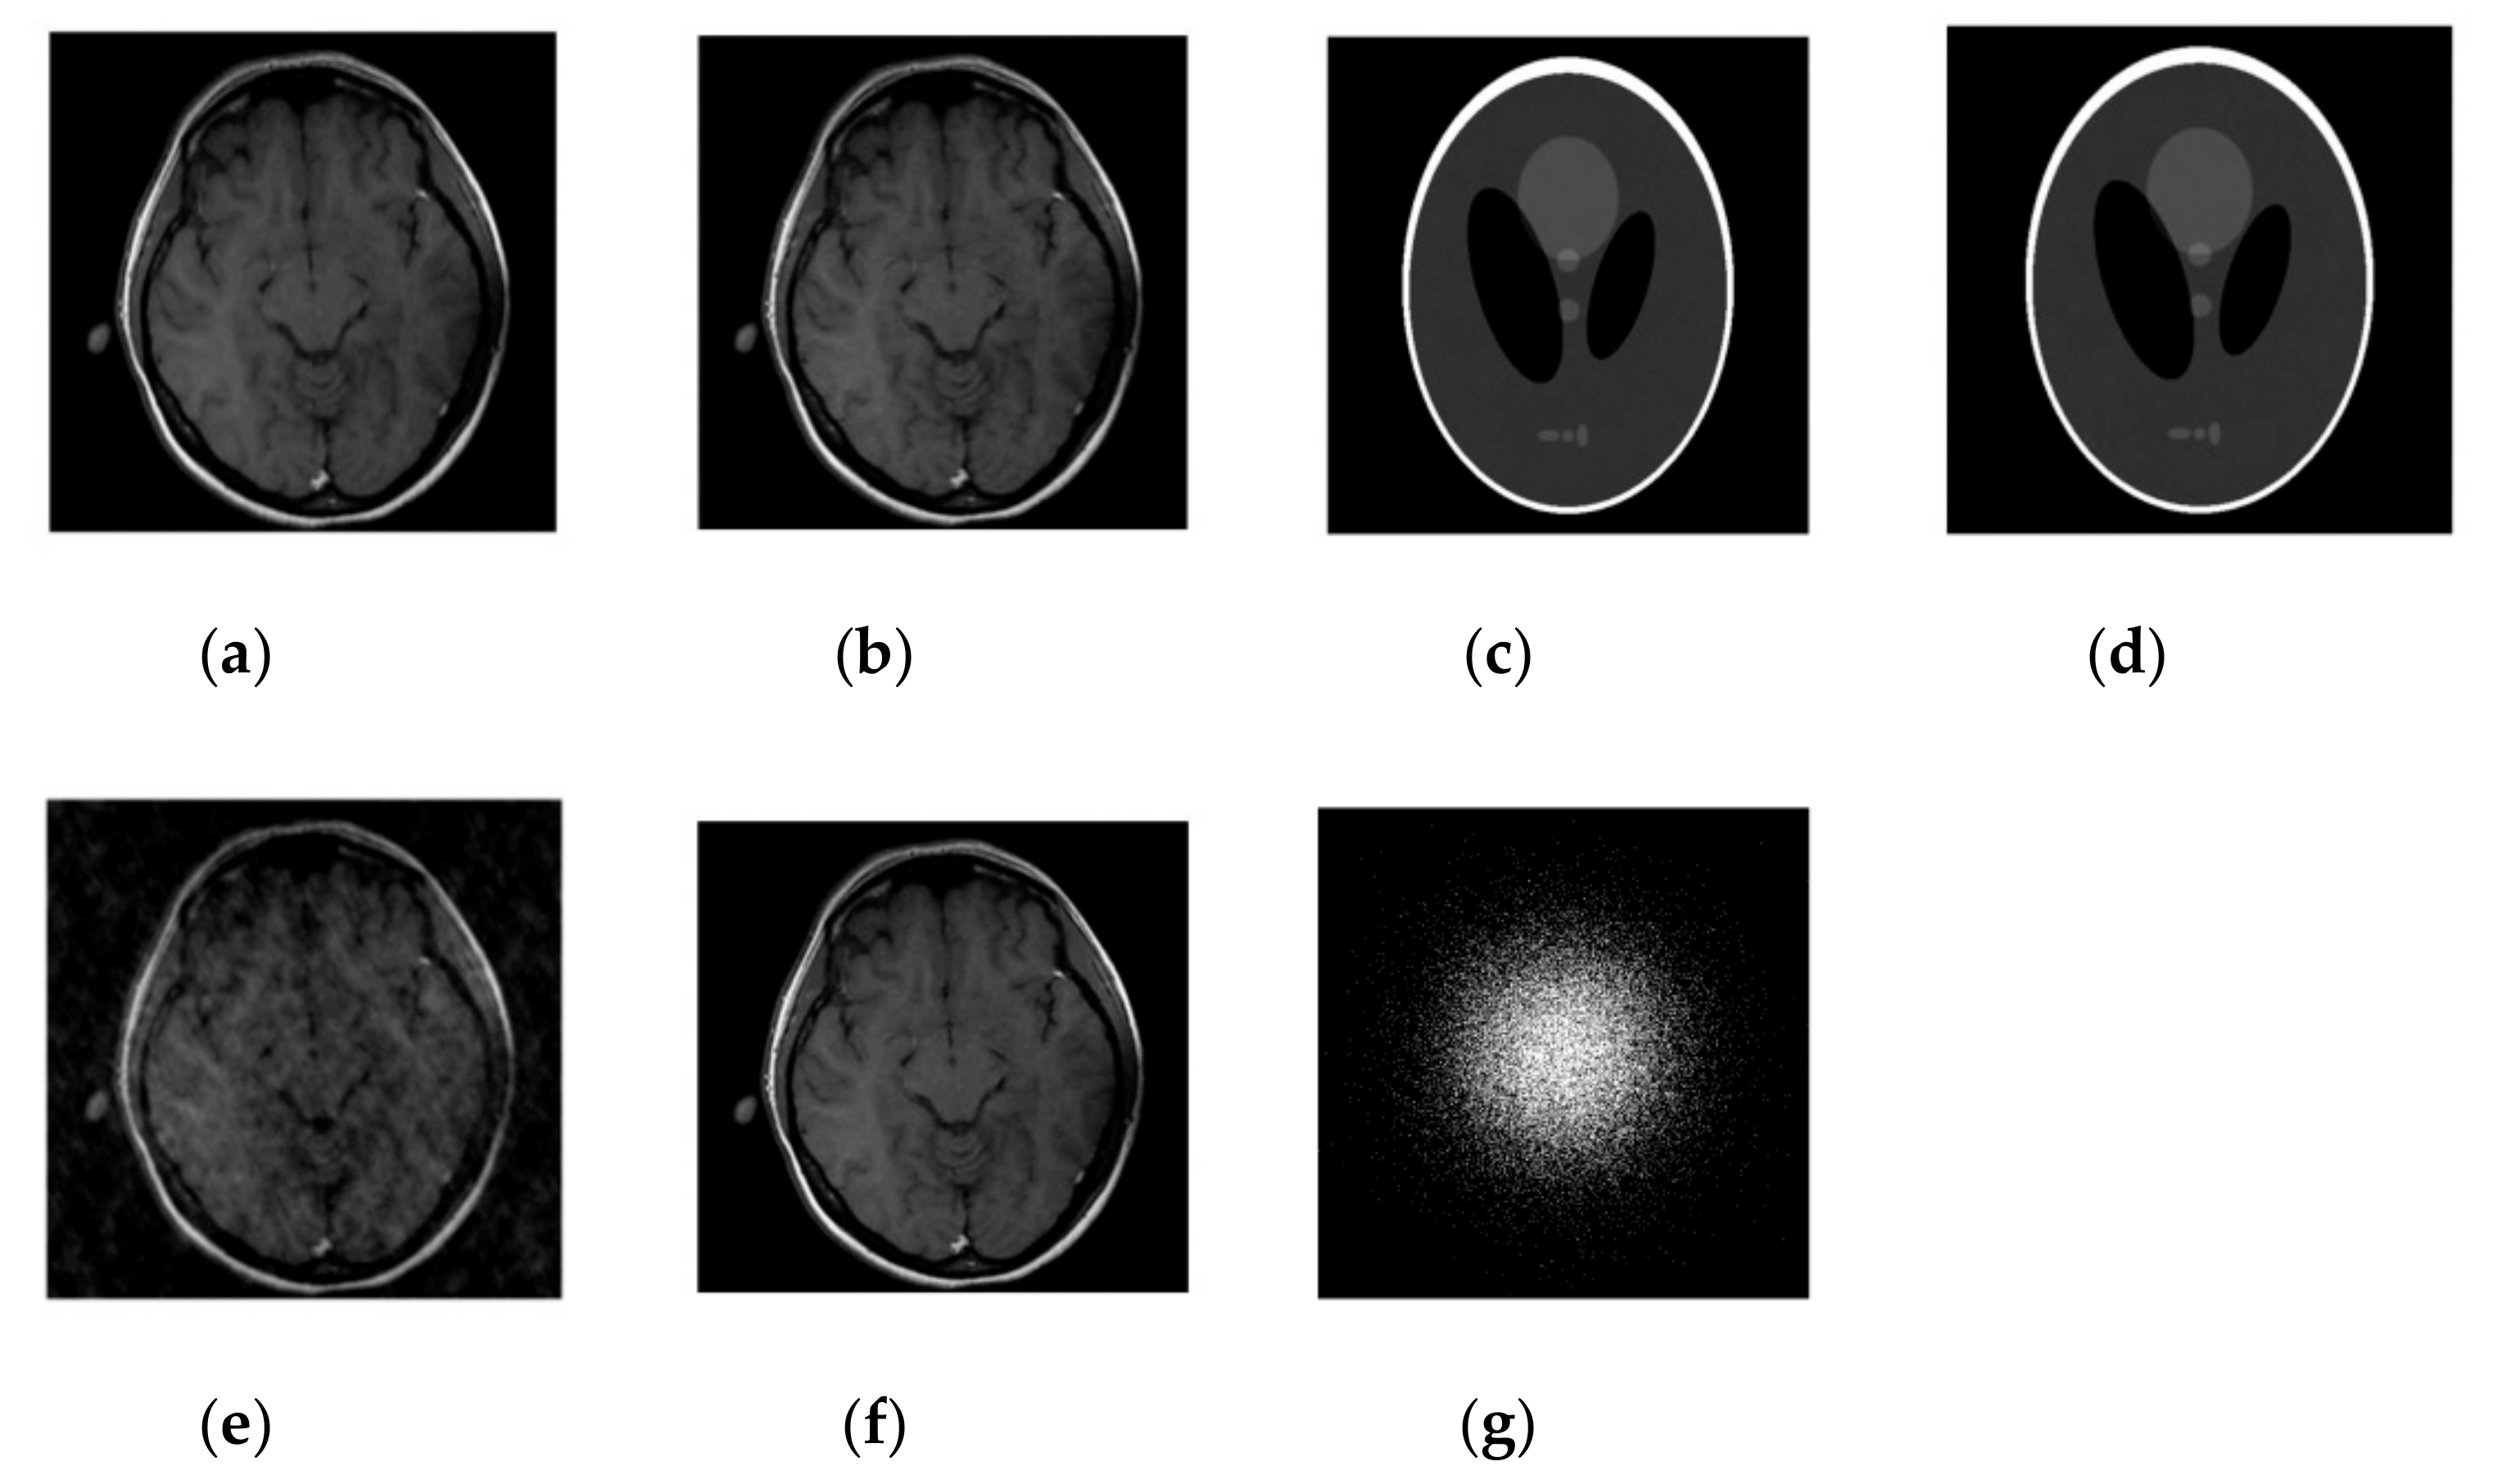

Figure 4. Images recovery in a noisy case. (a) Recovered MR image of a brain by SiFo; (b) Recovered MR image of brain by DLMRI; (c) Recovered MR image of phantom by SiFo; (d) Recovered MR image of a phantom by DLMRI; (e) sampling mask in k-space with 10 fold; (f) Reference MR image of a brain.

In this case, we added zero-mean white Gaussian fixed noise of standard deviation for all cases such that sigma = 10.2489 in k-space data. In the course of reconstruction update stage of the algorithm in (17), the noisy scenario involves weighted averaging in k-space. The performance of our technique on the fully sampled noisy image is observed by using a different sampling mask. Our process of reconstruction has sufficiently removed the noise and aliasing observed in the zero-filled result.

From Figure 3, the comparison of PSNR for both methods is observed for the reconstruction of the MR image. Our algorithm significantly removes aliasing and noise noticed in the zero filled result, hence providing a better reconstruction. The reconstruction error magnitude of the image for SiFo displays pixel errors of considerably reduced magnitude and fewer structure than that of DLMRI technique by Saiprasad et al. [22].

3.2.2. HFEN

The convergence rate has been observed to be efficient. If we compare the SiFo with DLMRI, the SiFo converges at the rate 0.95 whereas DLMRI stops at 1.14 (in the reconstruction of brain image) at the end of the executed number of iteration 15. This shows that the proposed algorithm outperforms DLMRI regarding reasonable noise. So image features for the reconstruction of the brain and phantom images are smooth, clear and free from the effect of aliasing and artifacts as shown in Figure 4.